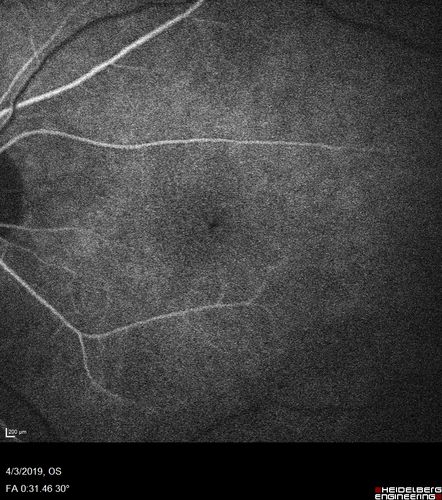

Stellate Non-heredtiary Idiopathic Foveomacular Retinoschisis (SNIFR)

77 year old man who is healthy and 6'6" tall with 20/40 vision and no complaints. OCT shows diffuse retinoschisis.